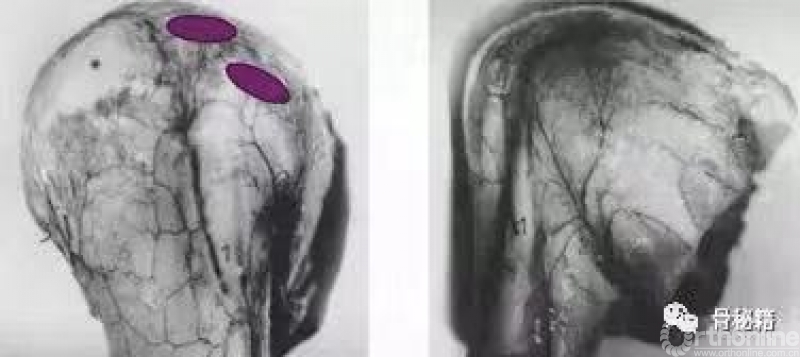

这是一个我们常见的肱骨近端骨折,我们可以看到外侧的大结节粉碎

中间有很多头内的缺损,常见的固定是将外侧复位之后通过钢板在外侧对剩余的头进行固定,这种偏心的固定在骨缺损的情况下通常很容易失败。

而我们应用髓内钉就是另外一种情况,通过头上较好骨质对主钉的把持来维持整个固定,这个病例为了很好的控制头的固定,使得进针点非常靠内,这样才能把持主头的骨折块,通过主钉来重建生物力学的稳定性,再通过锁定来重建大结节的部位,相对来说失败的几率更小一些